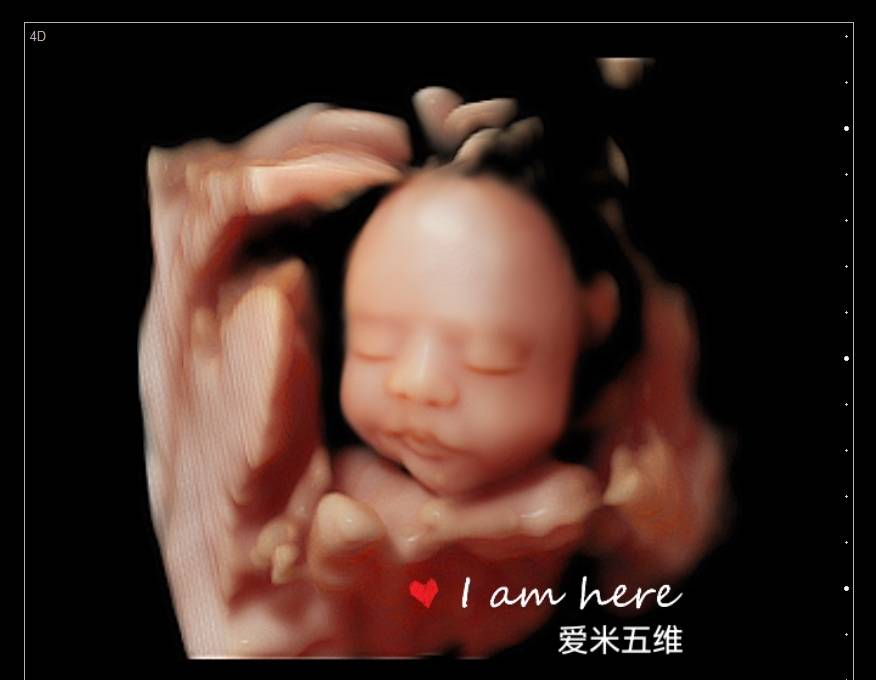

第一次五维看到了宝宝,好可爱,看的非常清楚,打印出来的照片也很清晰,第一次看到宝宝在肚子里的样子真的很激动,服务特别亲切,拍个五维还是很值得的

爱米孕婴摄影有着8年的拍摄历史,经验丰富、专业技术高超、并引进最新技术设备、呈现最完美影像照片,我们秉承着以客户满意为宗旨、资深影像师为您一对一的服务,宝妈可通过大屏幕清晰看到宝宝的各种动作及表情,让您感受与宝宝初次见面的激动,留下珍贵的瞬间!